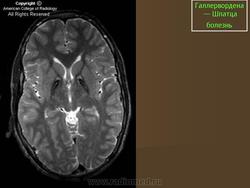

ГМ. Галлервордена - Шпатца болезнь. +

Галлервордена - Шпатца болезнь

Болезнь Галлервордена - Шпатца - наследственное заболевание экстрапирамидной системы, связанная с нарушением обмена железа и липидов и повреждением бледного шара и черной субстанции. Тип наследования аутосомно-рецессивный. При патоморфологическом исследовании характерным признаком является гиперпигментация бледного шара и черной субстанции. Обнаруживается пигментация коры полушарий большого мозга и таламуса. Пигмент находится внутри невронов и глиальных клеток, расположенных около сосудов; содержит железо (вместе с тем каких-либо нарушений обмена железа в организме не обнаружено). Наблюдаются утолщение и фрагментация аксонцилиндров в пораженных областях. Постепенно наступает дегенерация невронов коры полушарий большого мозга и мозжечка. Характеризуются нарастающей экстрапирамидной ригидностью, гиперкинезами (атетоз, торсионная дистония), затем развивается акинетико-ригидный синдром, пирамидная микросимптоматика, снижение интеллекта. Течение медленно прогрессирующее на протяжении 10 - 20 лет.

"Глаз тигра"-наглядно и красиво.

Вы правы. Выставил еще более нагладные исллюстрации.